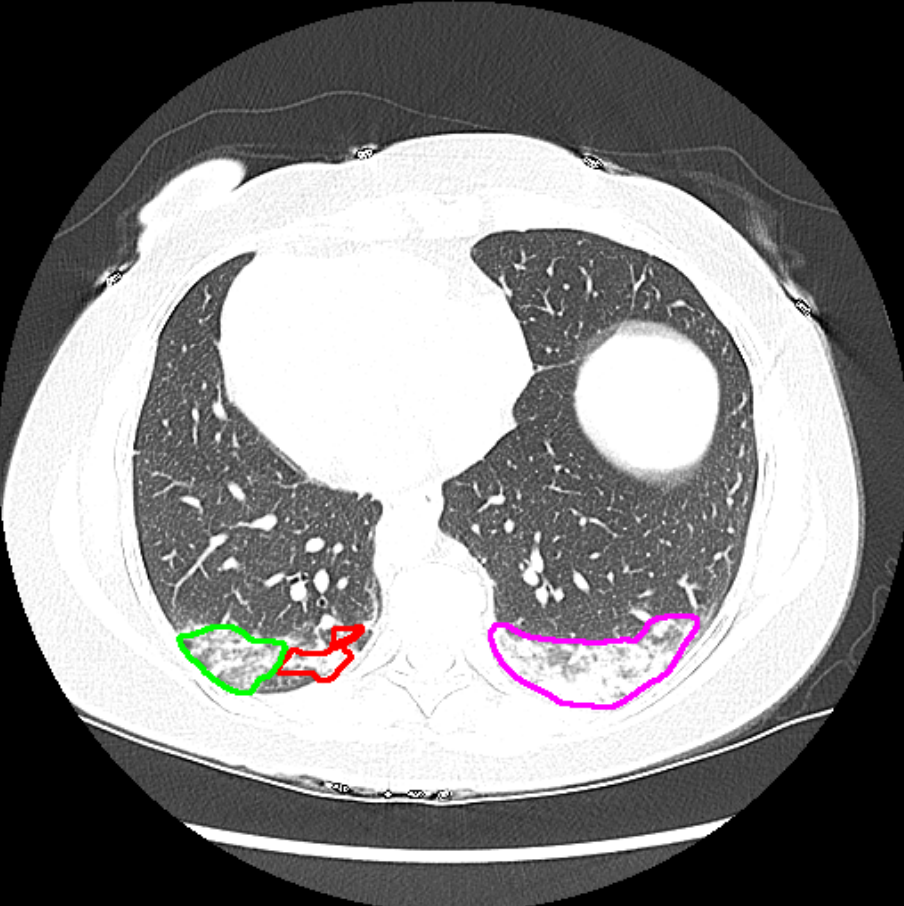

Detection of COVID lesions on lung CT

Deep learning